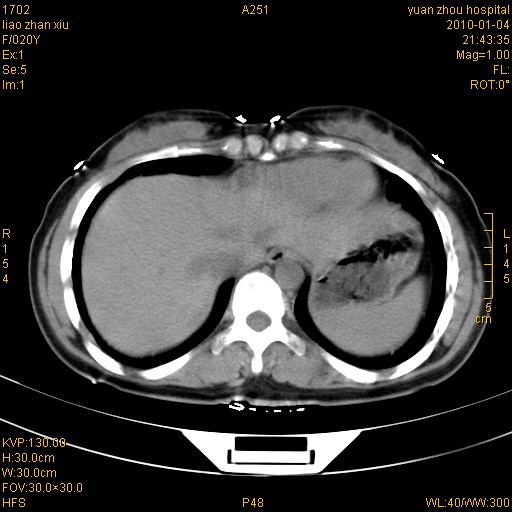

标题: CT23985:F20Y 外伤典型病例

左肾挫伤,包膜下积血。

左肾挫裂伤伴肾被膜下积血!另:肾周筋膜增厚!

1)左肾包膜下血肿。2)左侧肾挫伤可能;建议:行ct增强扫描检查。3)腰椎左侧横突骨折。

1、左肾挫伤,包膜下积血;

3、腹腔积气,考虑肠管破裂?